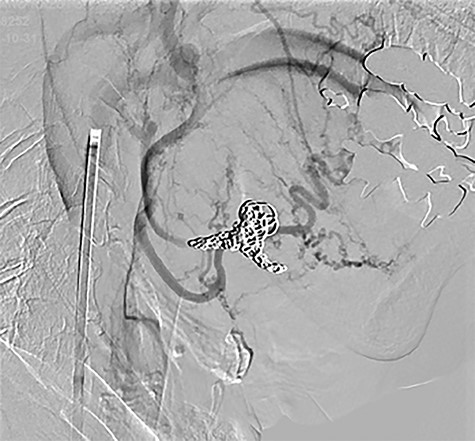

A parent vessel occlusion was performed with coils by endovascular surgeons from the distal to the proximal side of the aneurysm under local anesthesia (Fig. 4). After the endovascular trapping with coils, the facial mass was non-pulsatile.